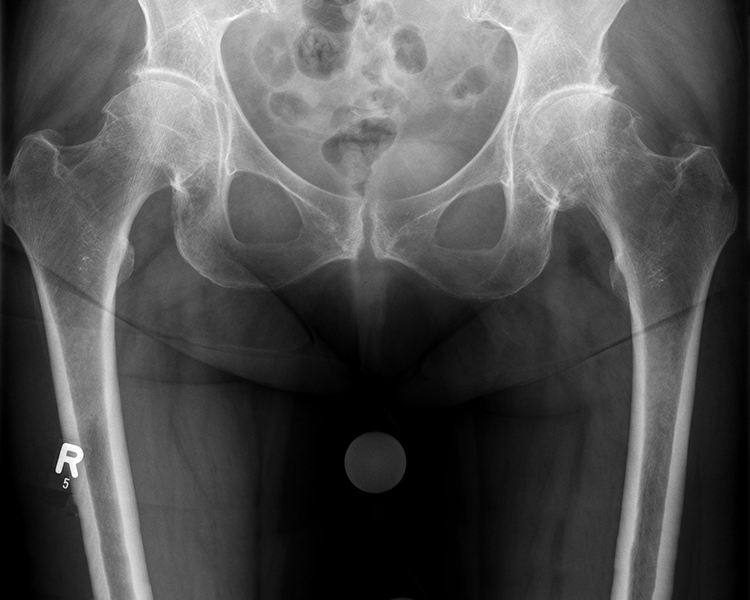

• Fortgeschrittene Hüftarthrose

• Hüftkopfnekrose

• Schwere Verletzungen

• Angeborene Deformitäten / Hüftdysplasie